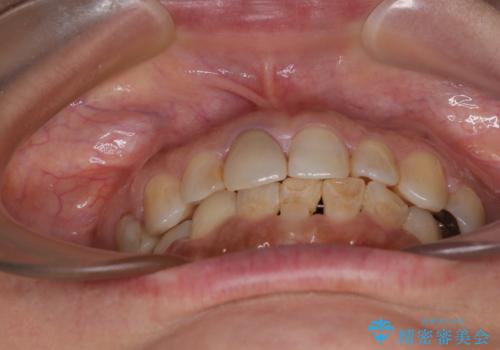

- 上下前歯のデコボコと、治療途中の歯を気にして来院された患者様です。

ご家族がインビザラインにて矯正治療を行っていたため、ご本人の希望によりインビザラインによるマウスピース矯正を行うこととしました。

根管治療が必要な歯は事前に処置を行った上で矯正治療を開始し、概ね歯列が整ったところでセラミッククラウンなどに置き換え、その後インビザラインを1セット使用して仕上げていくこととしました。